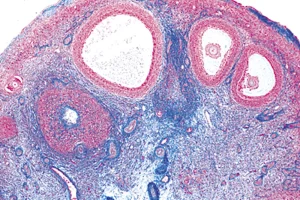

Ovary, cross-section, microscope slide

Ovary, cross-section, microscope slideSingle slide of an ovary showing the structures and cells that play a role in a woman’s follicle maturation and ovulation. The appearance of a micro-slide of the ovary is very similar to the illustrations you see in a biology book, so it does not require any medical training to find the structures and cells you have read about.